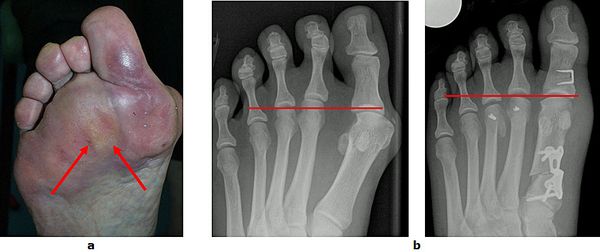

Abb.4: Klinische Dokumentation einer mittelschweren Hallux valgus Fehlstellung.

a Vor der Operation

b Rechter Fuß 7 Wochen postoperativ und linker Fuß 6 Monate postoperativ

Abb.10: a Schmerzhafte Schwielenbildung unter dem Vorfuß.

b Wiederherstellung der Längenverhältnisse zwischen dem ersten, zweiten und dritten Strahl durch eine Rückverlagerung der Mittelfußköpfchen zwei und drei. Zeitgleich wurde auch der Hallux valgus korrigiert.